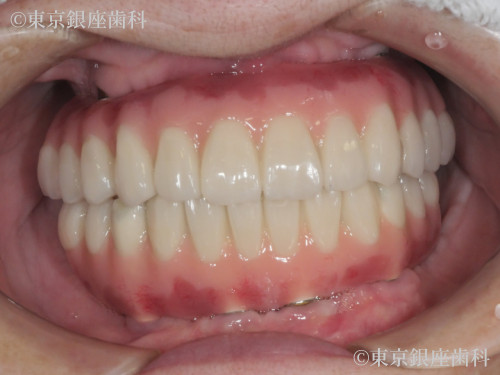

Before

After

総入れ歯が合わず不便を感じていたが、上下ワンデイインプラントを選択。上顎には6本の埋入と骨補強を併用し、計画通りに進行。噛み合わせも改善し自然な見た目を取り戻した。

上下ワンデイインプラント(インプラント6本+骨補強)